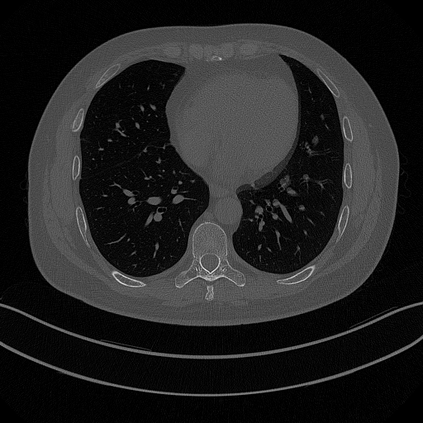

CT reconstruction provides radiologists with images for diagnosis and treatment, yet current deep learning methods are typically limited to specific anatomies and datasets, hindering generalization ability to unseen anatomies and lesions. To address this, we introduce the Multi-Organ medical image REconstruction (MORE) dataset, comprising CT scans across 9 diverse anatomies with 15 lesion types. This dataset serves two key purposes: (1) enabling robust training of deep learning models on extensive, heterogeneous data, and (2) facilitating rigorous evaluation of model generalization for CT reconstruction. We further establish a strong baseline solution that outperforms prior approaches under these challenging conditions. Our results demonstrate that: (1) a comprehensive dataset helps improve the generalization capability of models, and (2) optimization-based methods offer enhanced robustness for unseen anatomies. The MORE dataset is freely accessible under CC-BY-NC 4.0 at our project page https://more-med.github.io/